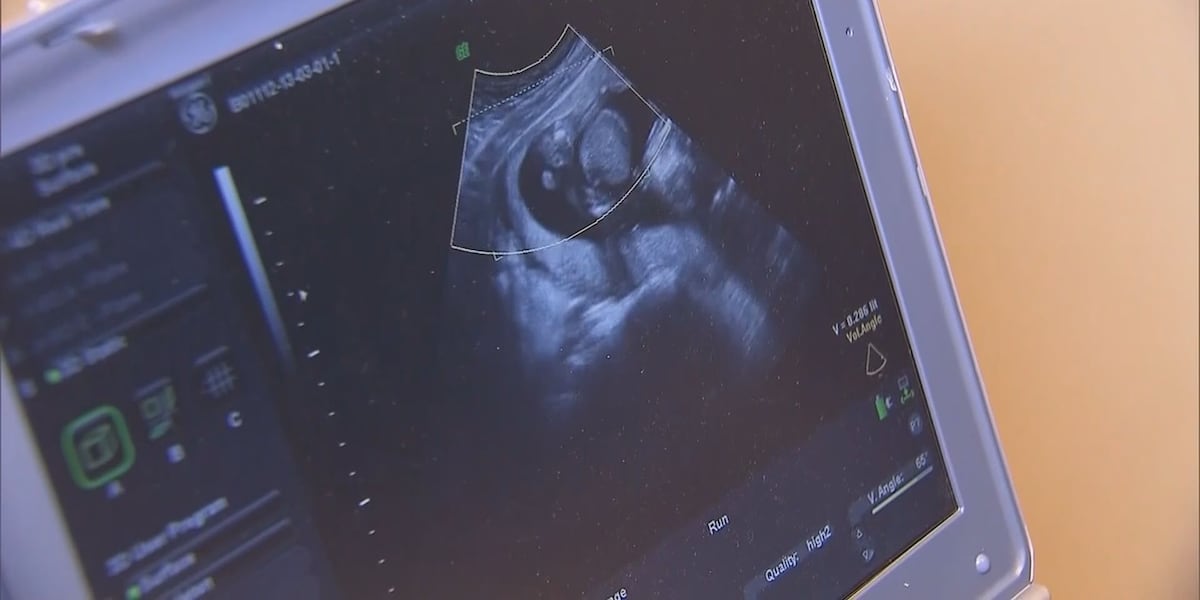

COLUMBIA, S.C. (WRDW/WAGT) - A group of South Carolina lawmakers voted against advancing what would’ve been the nation’s most restrictive bill against abortion.

The South Carolina Senate Medical Affairs Subcommittee voted 3-2 against the bill, S.323, after a meeting on Tuesday. While the bill’s immediate future is unclear, it could be revived in the future.

It’s a setback for a proposal that, if fully passed, would have allowed judges to sentence women to years in prison for abortions, and also restricted the use of IUDs and in vitro fertilization . It would’ve also banned all abortions unless the woman’s life is threatened.

Currently, South Carolina’s “heartbeat” law outlaws abortions after cardiac activity is detected, typically at around six weeks. It also allows abortions for ra